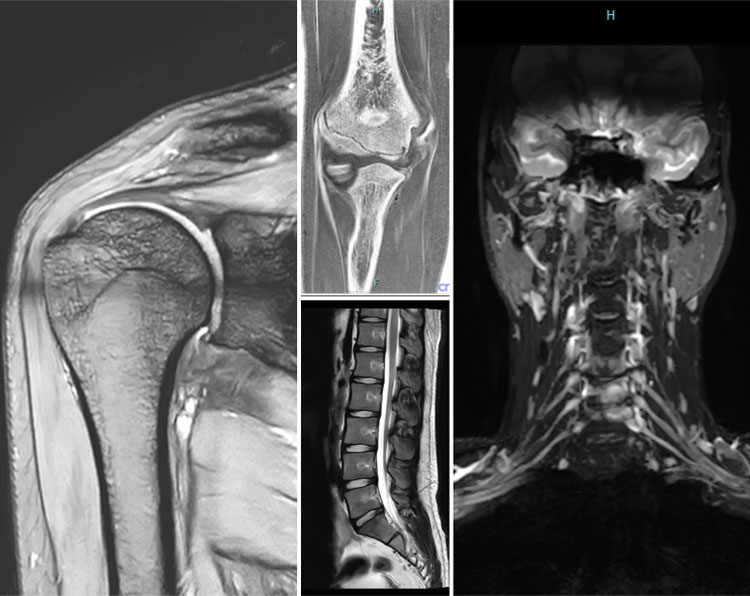

2高性能MRIを完備

「レントゲンやエコーでは異常なしと言われたのに、痛みは消えない」- そんな経験はありませんか?

靭帯・軟骨・神経・椎間板といった「軟部」組織はレントゲンで写らず、「深部・骨内」の異常はエコーで確認しにくいため、原因を特定できないケースが多くあります。

当院は整形外科クリニック内に、高解像度の「高性能」MRI を完備しており、レントゲンやエコーでは見つかりにくい細かな異常まで検出することができます。

30 分ほどの検査時間によって、正確な診断から最適な治療へつなげることができ、「原因不明のまま薬やリハビリだけが続く」という不安を解消しやすくなります。

当院では、MRI検査後はその日のうちに結果をお伝えし、より速やかに治療方針をご提案できることが特徴ですが、正直に申し上げますと、精密検査のためMRIの検査時間は長くなりがちです。

その分、「やっと原因がわかった」と安心していただけるよう、検査の質と深さにこだわって丁寧に診療しております。